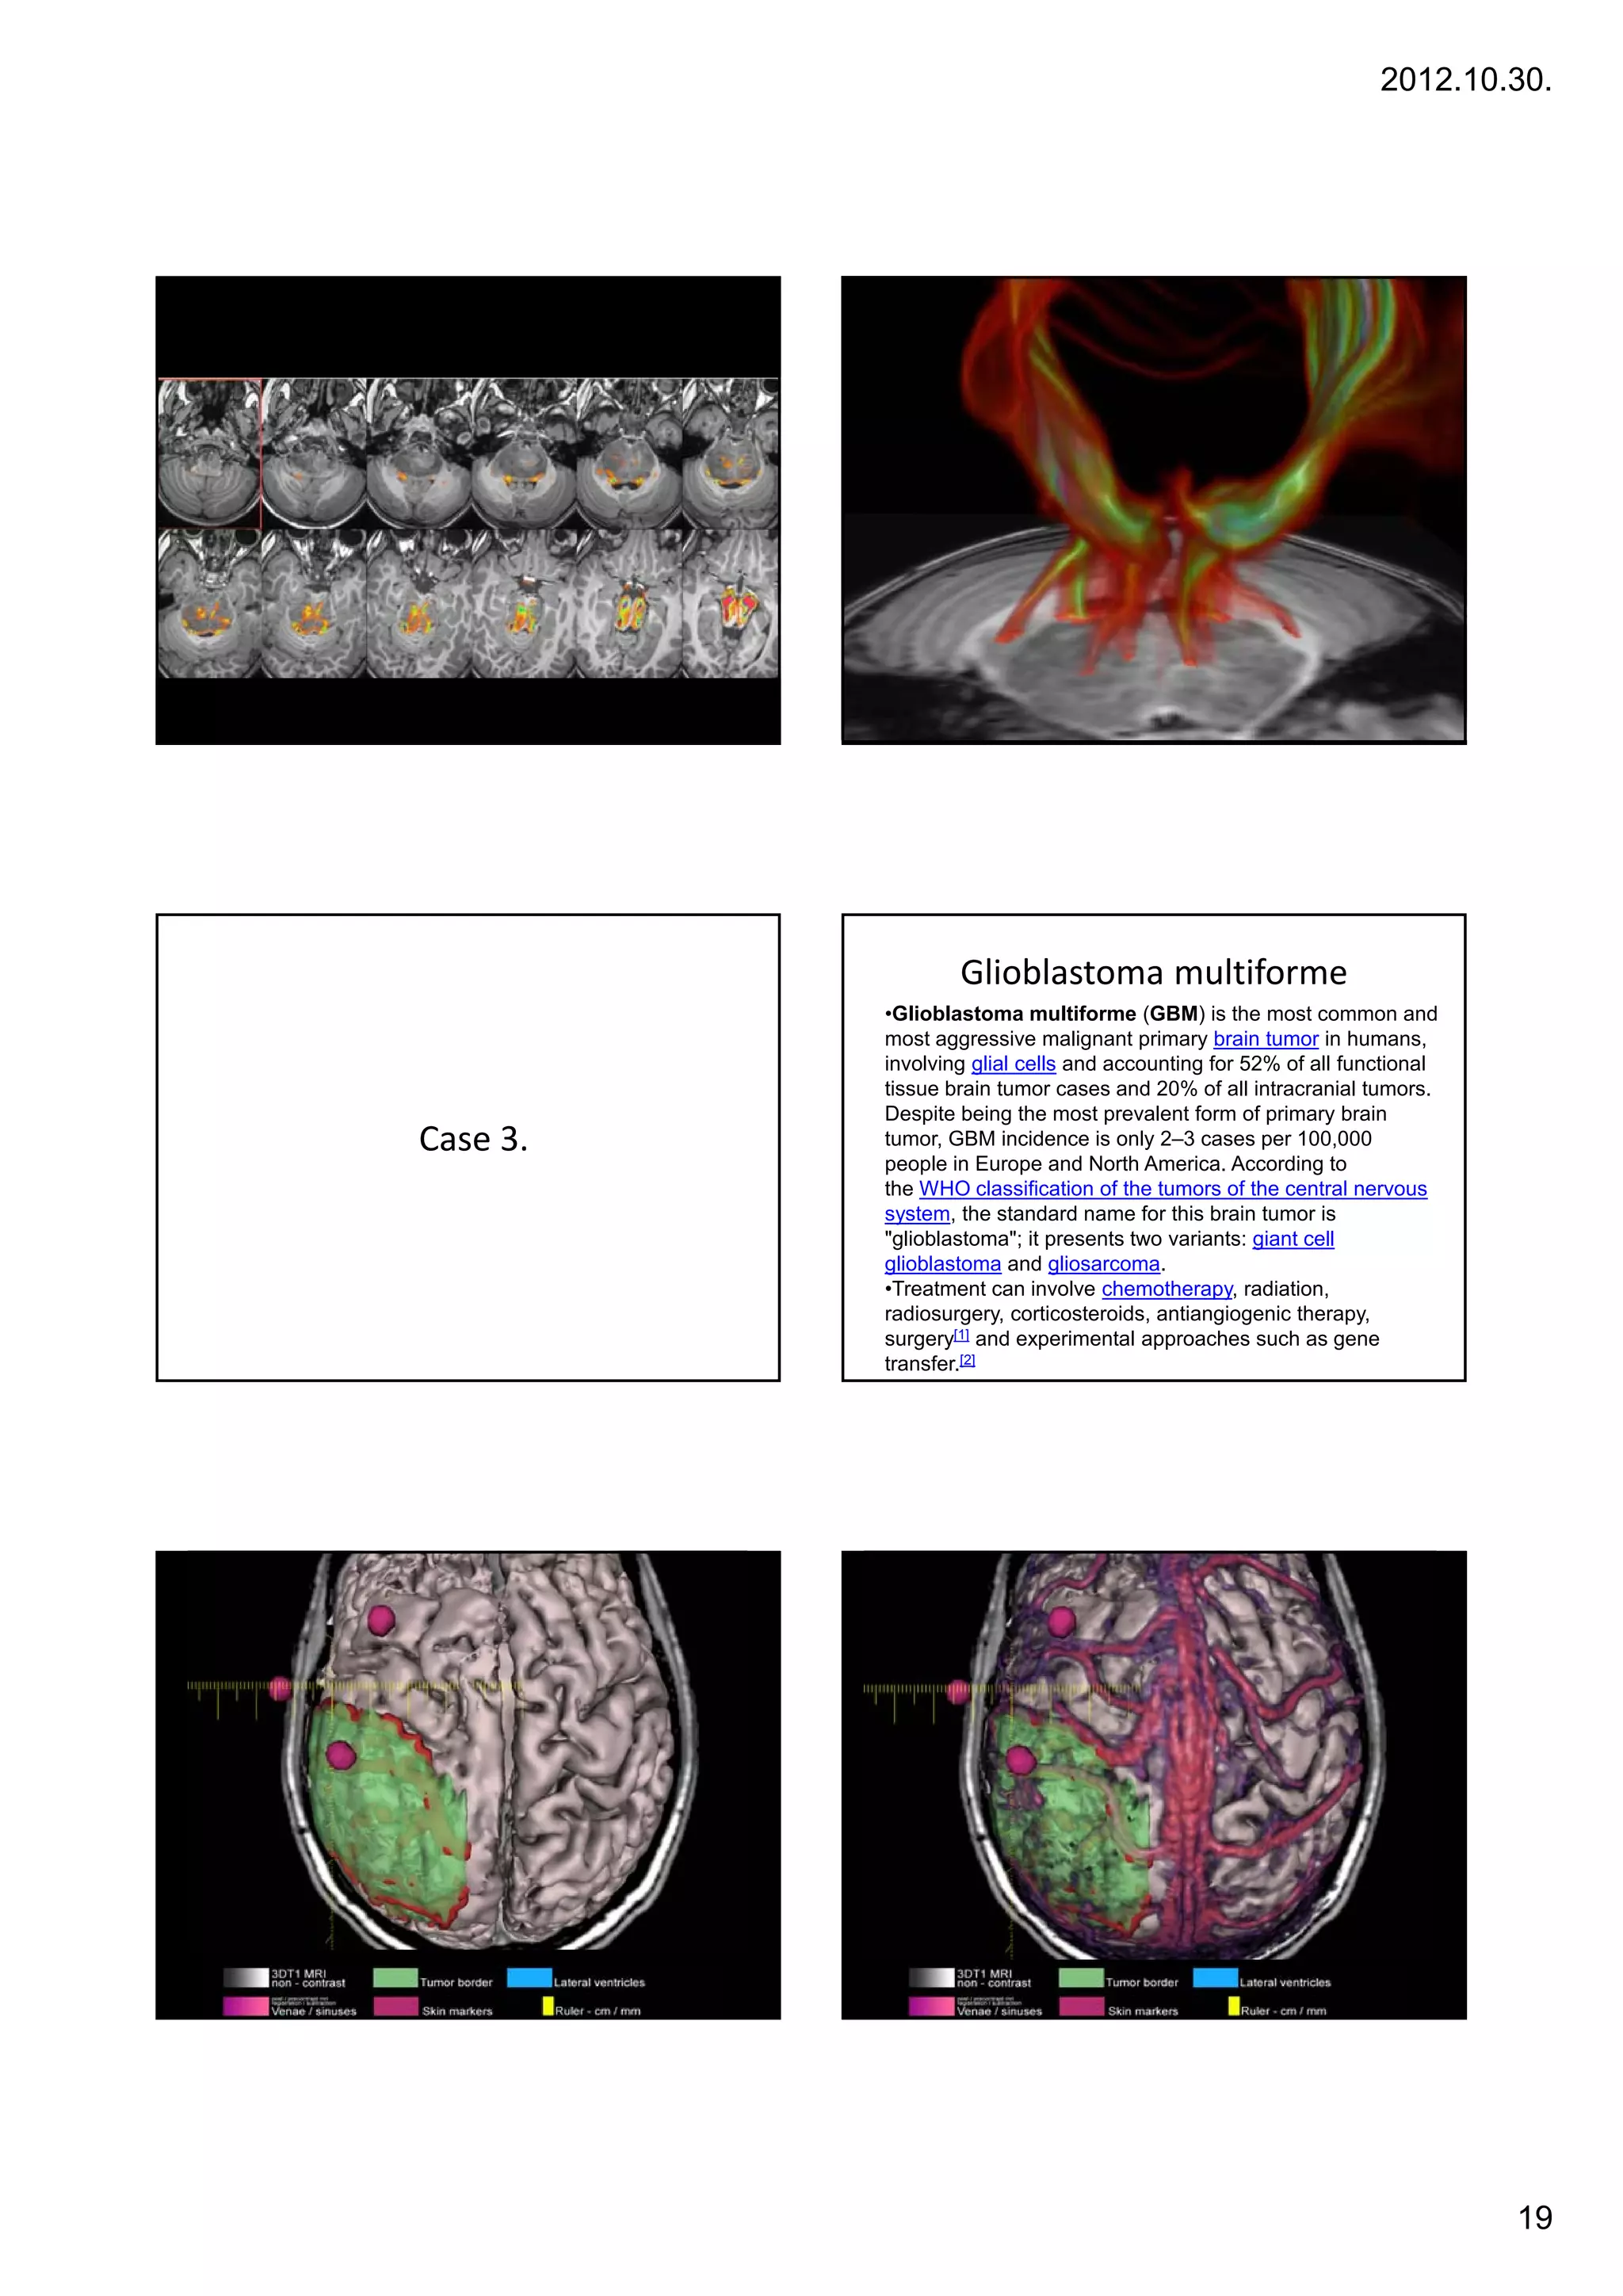

Glioblastoma multiforme

•Glioblastoma multiforme (GBM) is the most common and

most aggressive malignant primary brain tumor in humans,

involving glial cells and accounting for 52% of all functional

tissue brain tumor cases and 20% of all intracranial tumors.

Despite being the most prevalent form of primary brain

Case 3.   tumor, GBM incidence is only 2–3 cases per 100,000

,                       y            p       ,

people in Europe and North America. According to

the WHO classification of the tumors of the central nervous

system, the standard name for this brain tumor is

"glioblastoma"; it presents two variants: giant cell

glioblastoma and gliosarcoma.

•Treatment can involve chemotherapy, radiation,

radiosurgery, corticosteroids, antiangiogenic therapy,

surgery[1] and experimental approaches such as gene

transfer.[2]

19